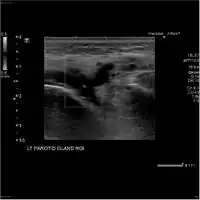

Acute left parotid sialadenitis